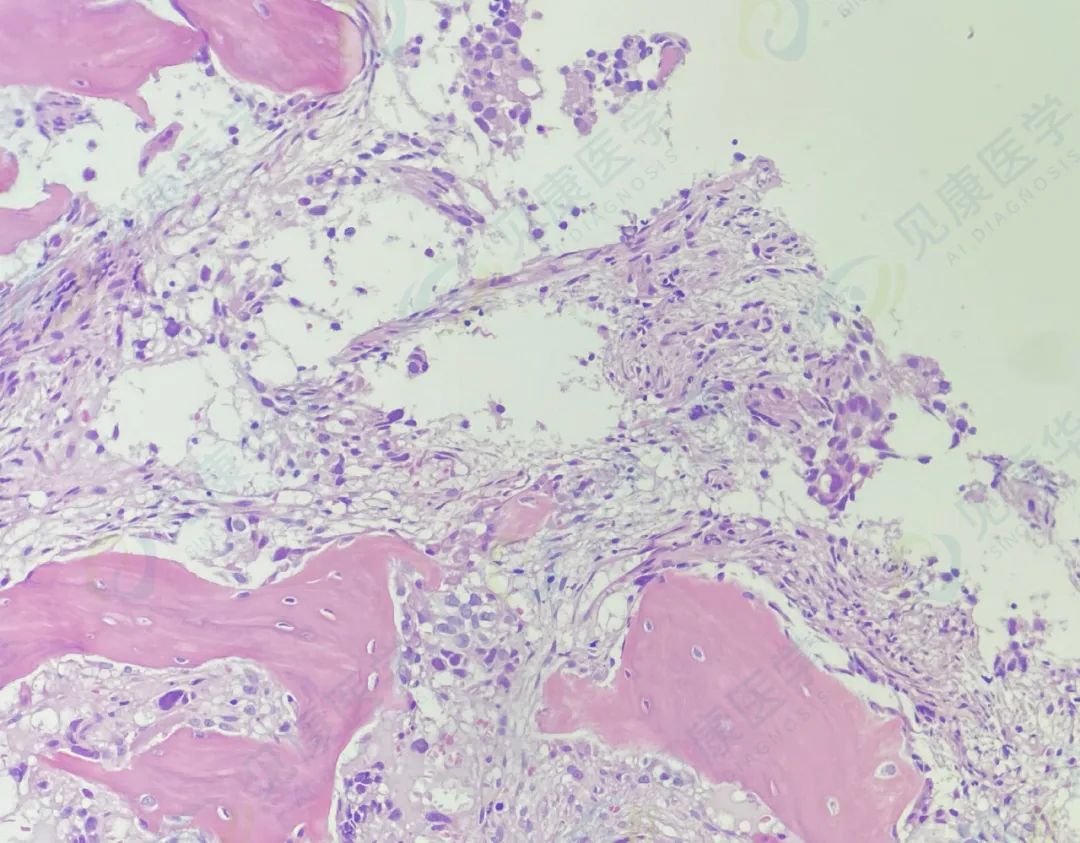

病理HE染色

病理

AML-M2伴骨髓转移癌